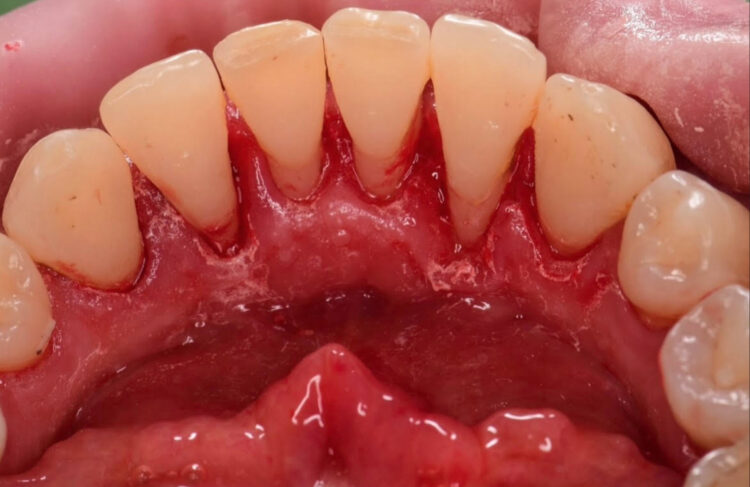

↓こちらがクリーニング積み重ねでの歯周病の菌の変化です。

定期的なクリーニングによって歯周病菌を減らし歯周病のリスクをガッと下げられます!